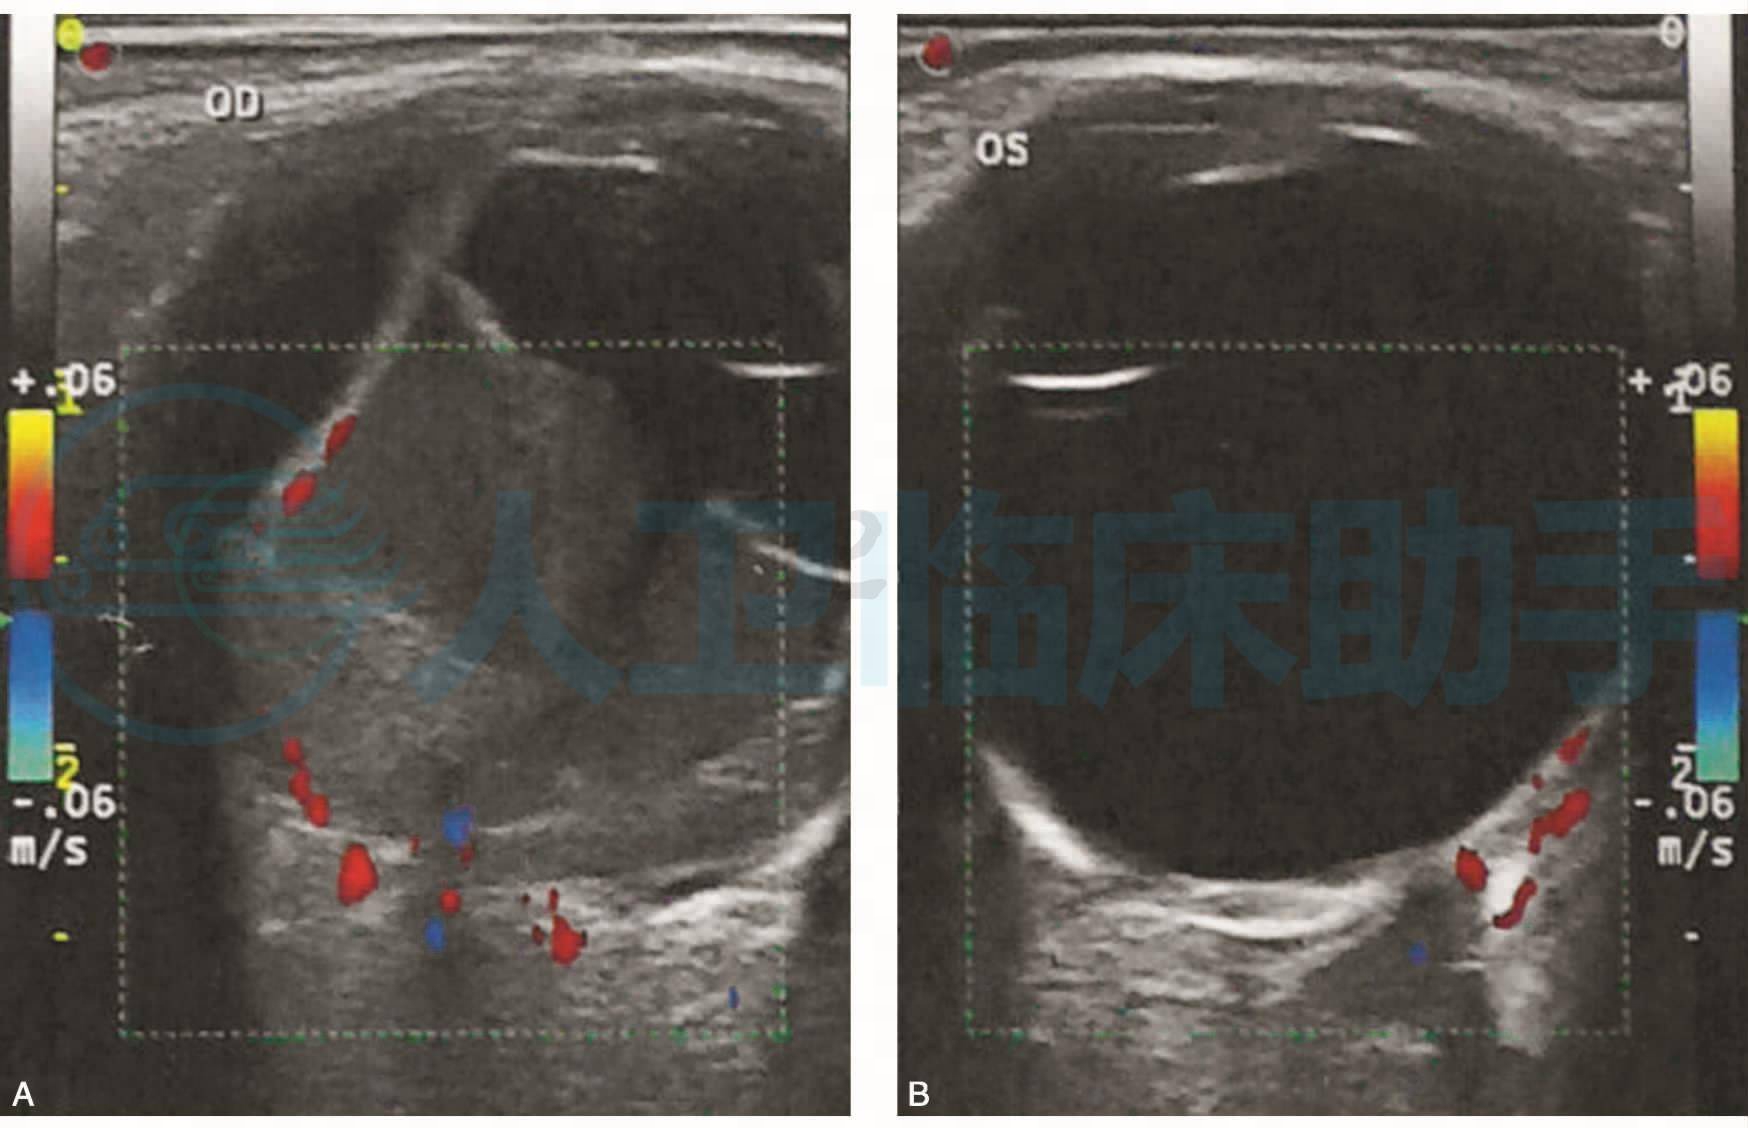

图1 患者女性,61岁,眼部彩色多普勒超声检查

A.右眼玻璃体内致密点条状回声及带状回声,与视盘回声相连动度(+),后运动(-),其上可见血流信号,可探及带状回声与周边球壁回声相连;B.左眼球内未见异常回声及异常血流信号